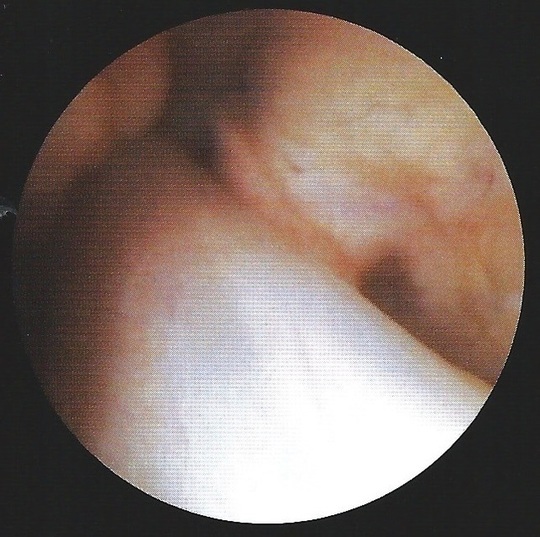

膝の靭帯(右膝を前方から見たところ)